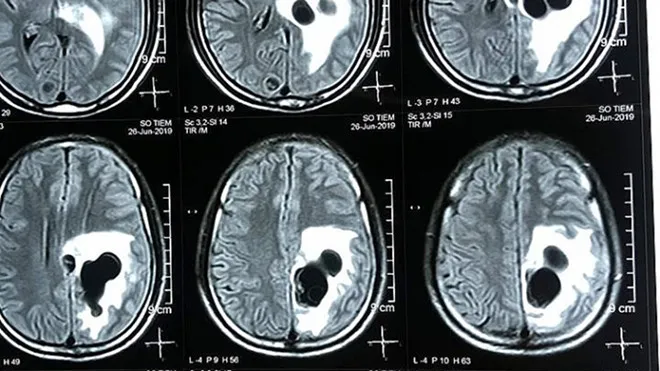

Tại bệnh viện, qua thăm khám và chụp CT não, các bác sĩ phát hiện có 5 ổ sán nằm rải rác trong não anh S., trong đó có một ổ sán lớn trên đỉnh não, gây phù não. Ngay lập tức, bệnh nhân được các bác sĩ chỉ định can thiệp ngoại khoa, phẫu thuật và lấy các ổ nang sán khỏi não. Sau ca mổ, hiện bệnh nhân S. đã hồi phục, tỉnh táo, hết triệu chứng bị liệt và bắt đầu đi lại được.